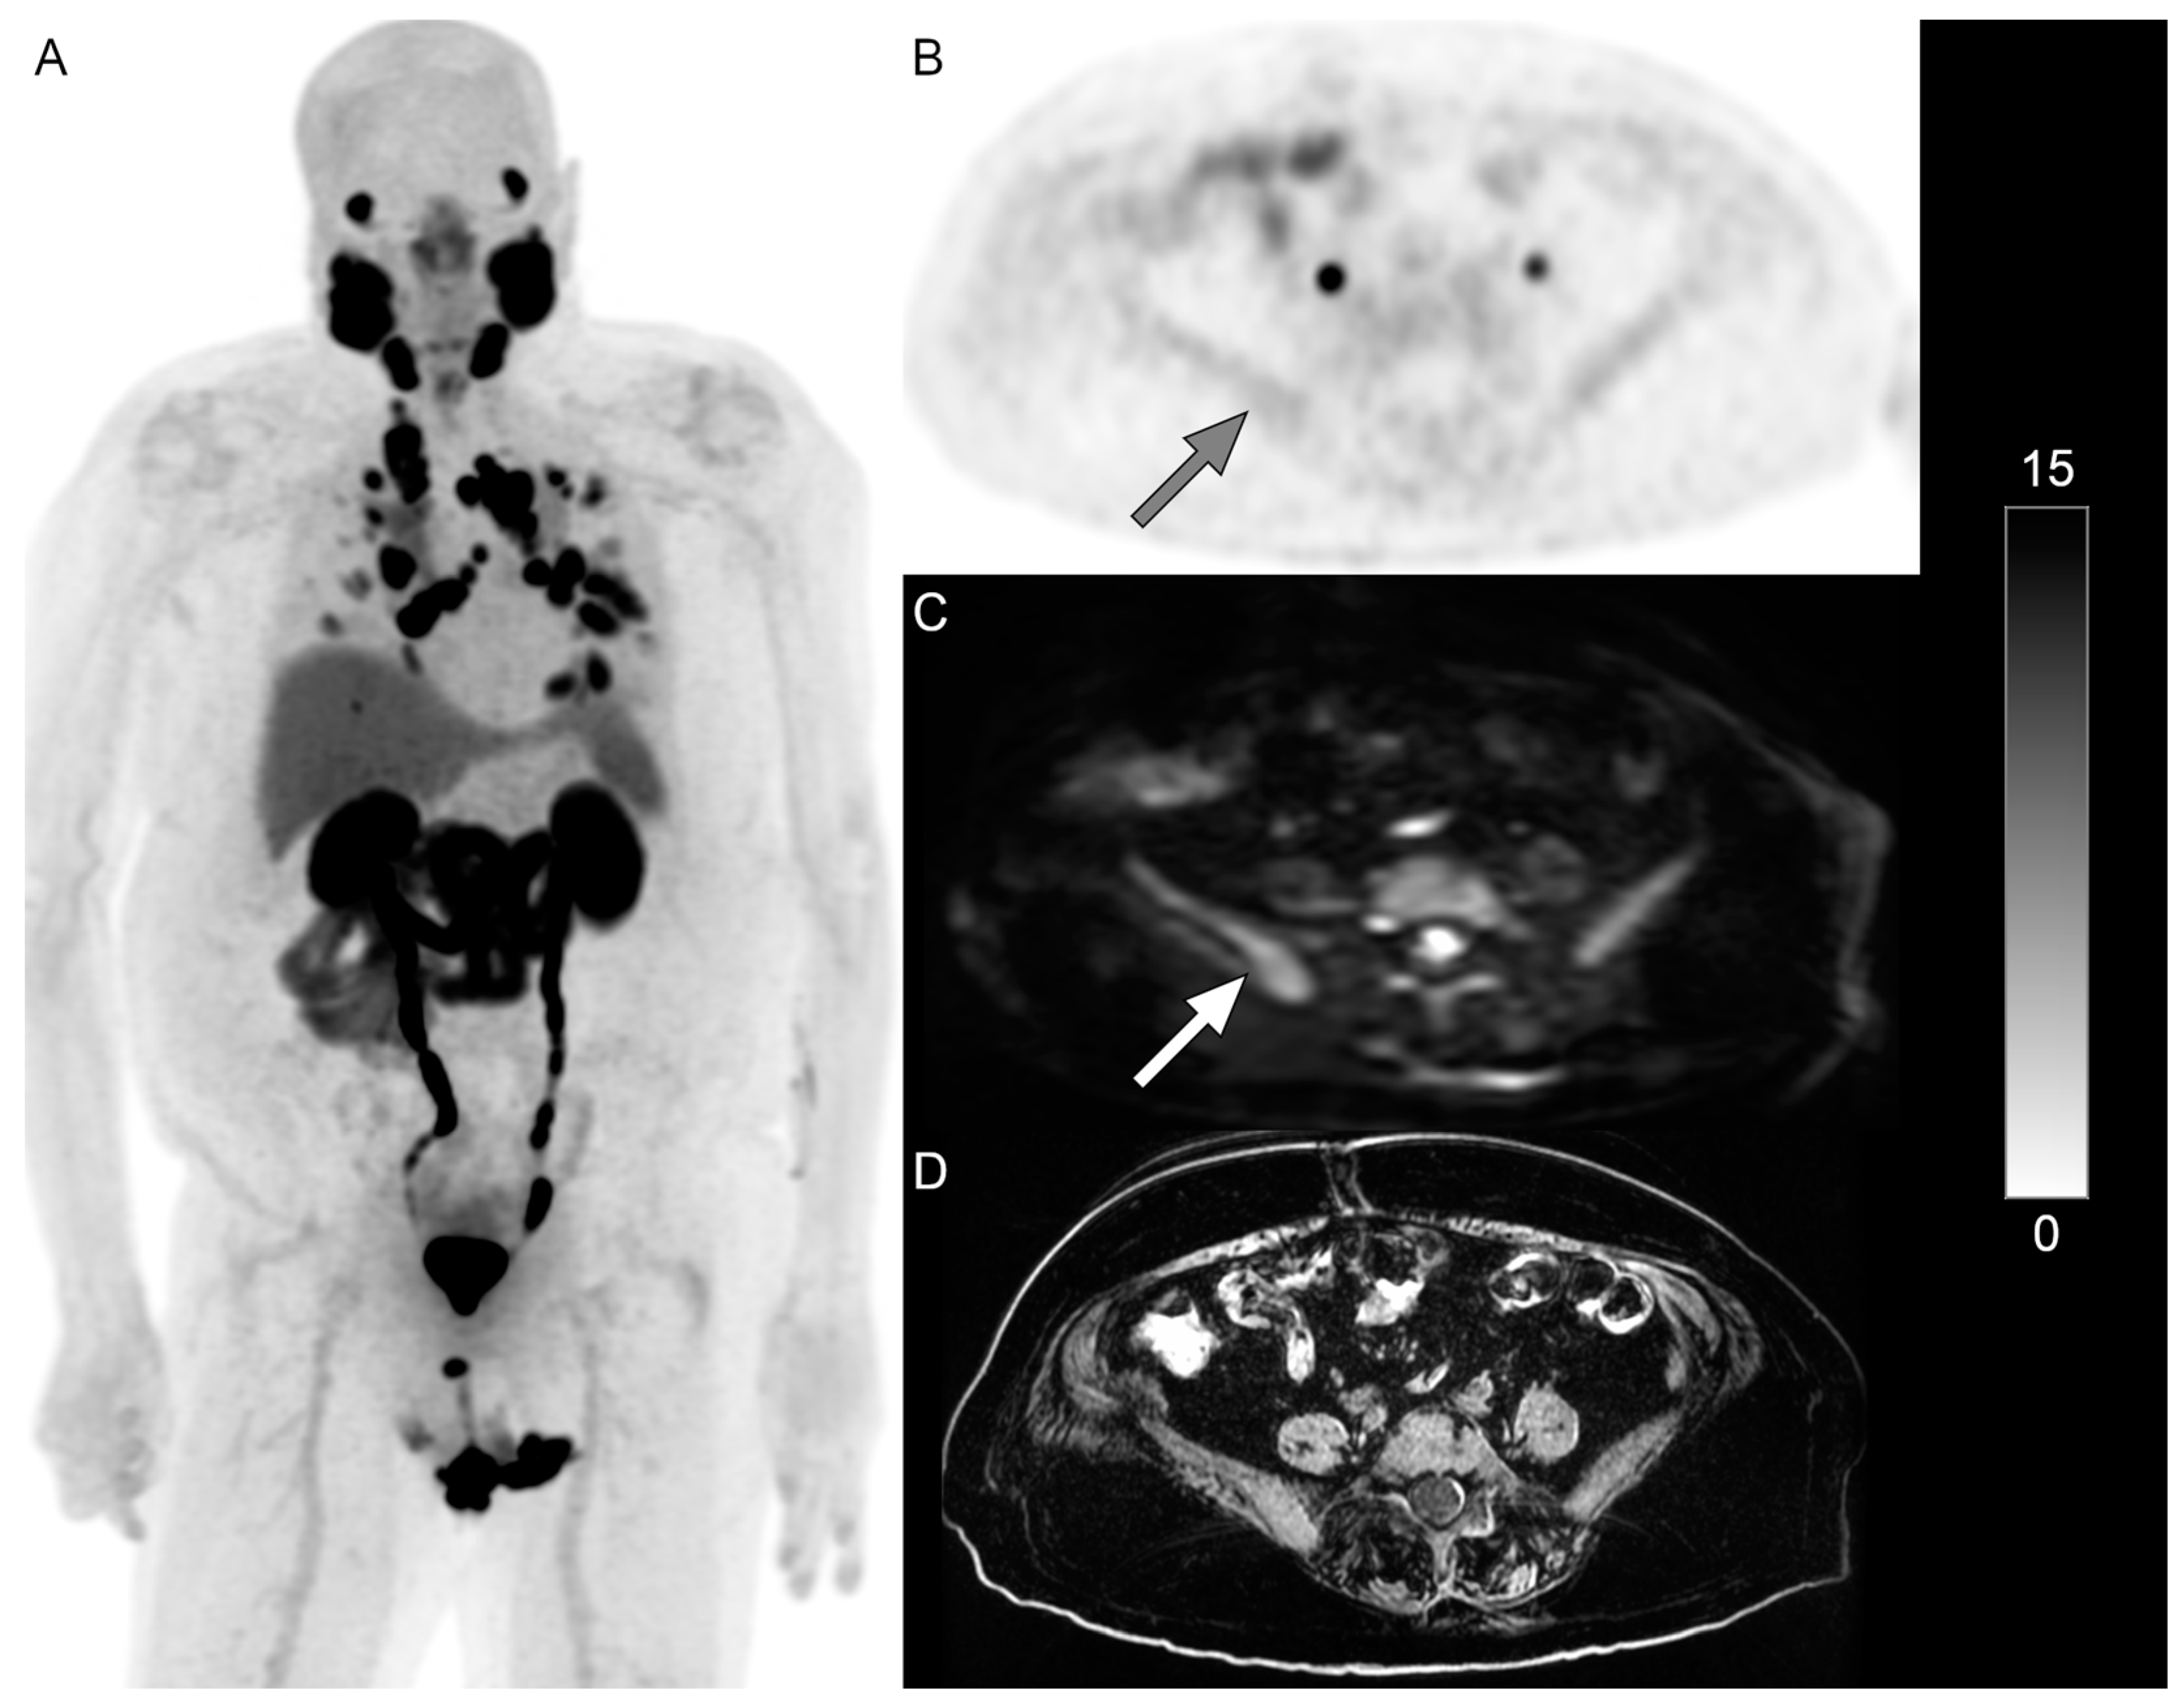

Excluding lymph nodes, DWI MRI identified additional lesions not identified on the PSMA PET in 14% (n = 6) of patients. It was noted that while 46% of patients in this analysis received RLT, none of these six patients with non-nodal mismatched disease received RLT. Figure 1 and Figure 2 show examples of patients with PSMA-negative disease that were identified on DWI.

Figure 2. PET/MRI in a 78-year-old man with mCRPC with extensive mediastinal and supraclavicular nodal metastases ((A), whole-body 18F-DCFPyL PSMA PET maximum-intensity projection image). Only minimal PSMA activity was identified in the pelvic bones ((B), gray arrow); however, osseous metastases were identified on b = 800 DWI ((C), white arrow). A T1-weighted image (D) is also shown. The scale bar of PET activity (SUVs) is on the right. RLT was planned, but he died a month later prior to receiving RLT.